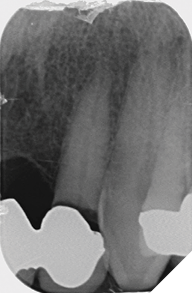

Radiographic examination shows the upper left lateral incisor tooth has decayed through and through and the upper right central incisor tooth is heavily root treated and filled (Figs. 1-2).

Fig. 1

Fig. 2